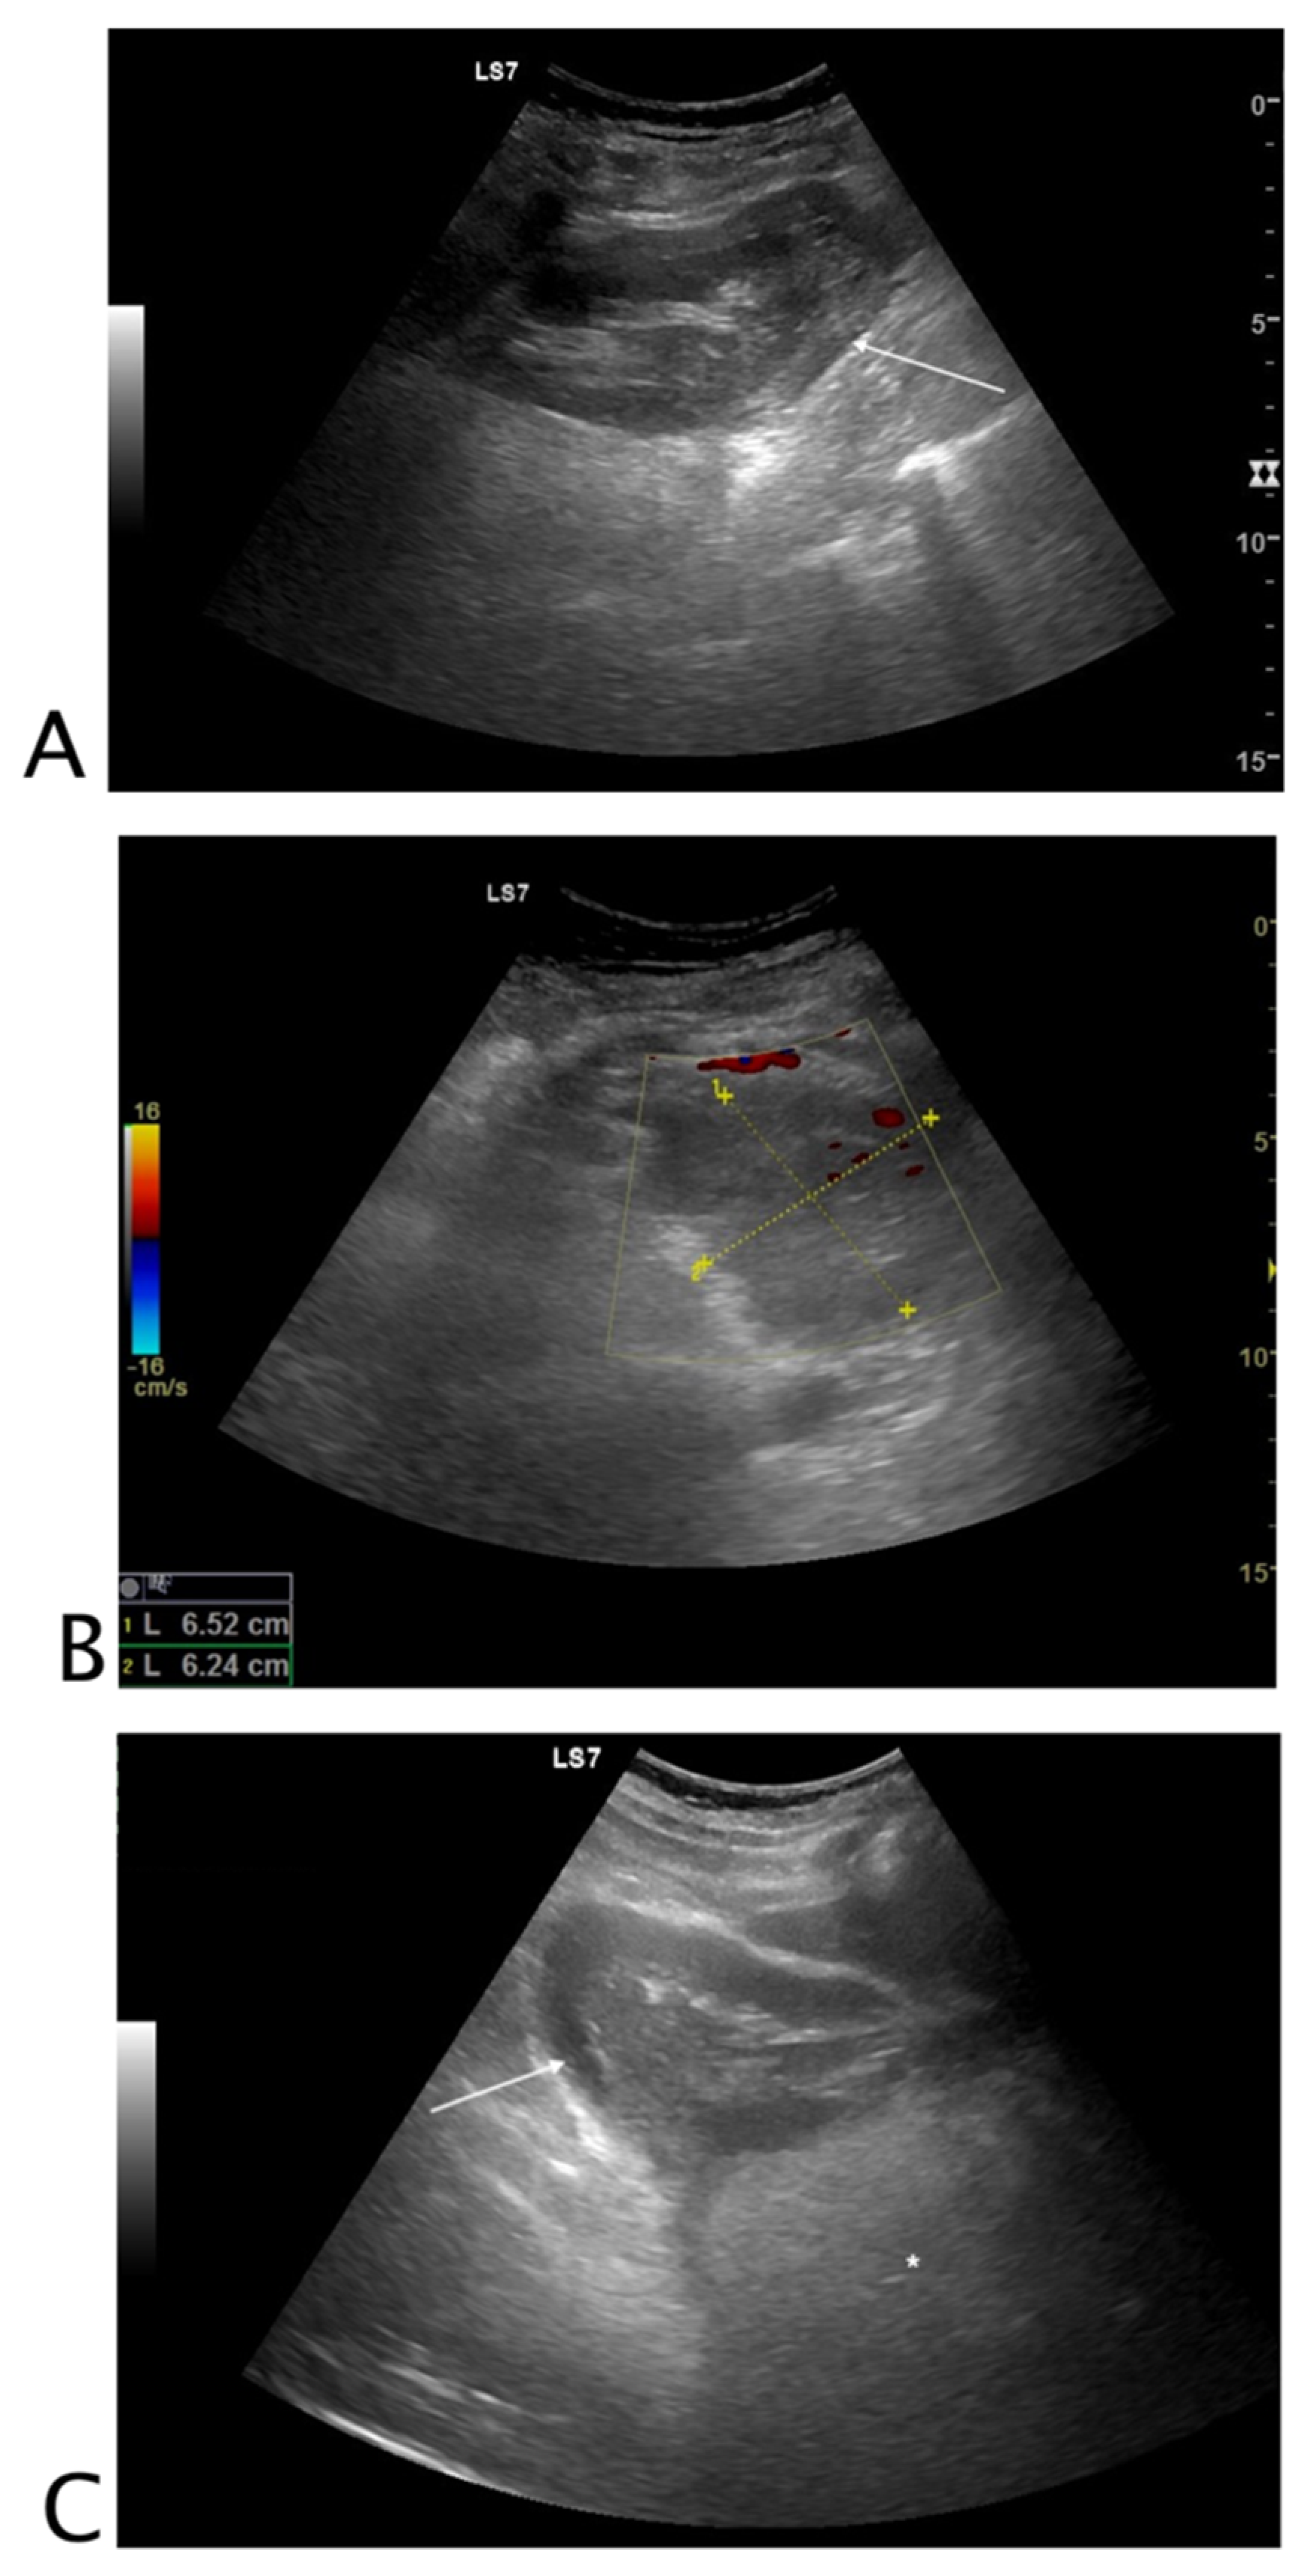

2.2.2. Urinary Tract

2.3.2. Urinary Tract

- Castelletto, S.; Giudice, C.A.; Orso, D.; Copetti, R. A Preliminary Investigation on the “Swinging Kidney”: A Sonographic Sign Useful for Diagnosing Renal Colic. J. Diagn. Med. Sonogr. 2022. [Google Scholar] [CrossRef]